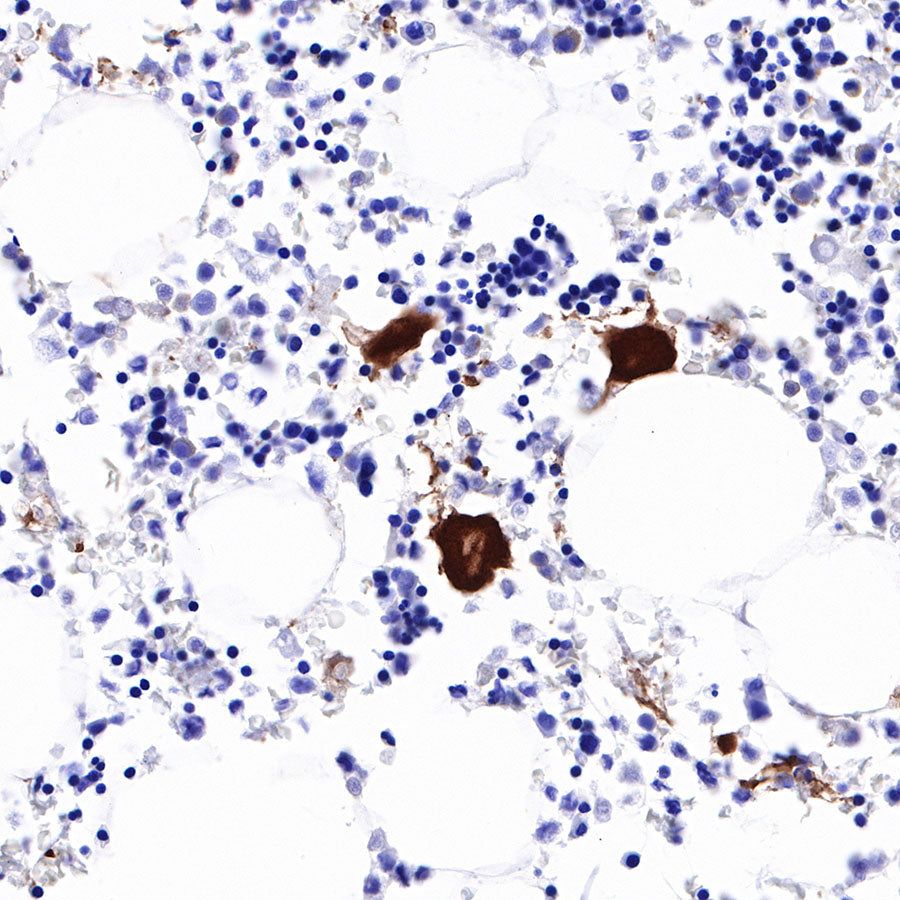

Immunohistochemistry

IHC shows positive staining in paraffin-embedded human bone marrow. Anti-CD226 antibody was used at 1/1000 dilution, followed by a HRP Polymer for Mouse & Rabbit IgG (ready to use). Counterstained with hematoxylin. Heat mediated antigen retrieval with Tris/EDTA buffer pH9.0 was performed before commencing with IHC staining protocol.